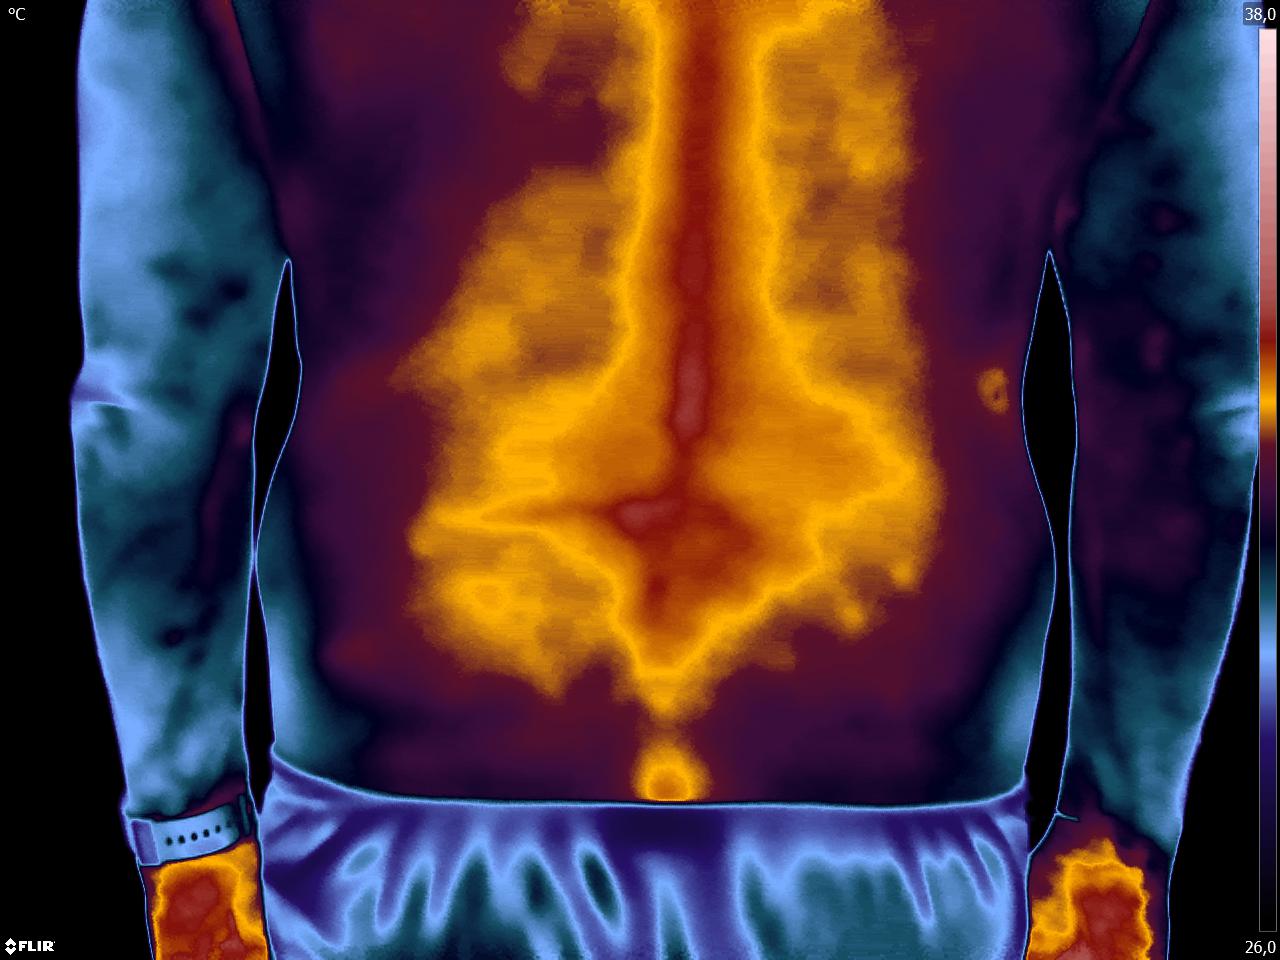

Caros colegas fisioterapeutas e terapeutas ocupacionais, vocês sabiam que, por meio do estudo da Termofuncional, é possível identificar alterações térmicas […]

Caros colegas fisioterapeutas e terapeutas ocupacionais, vocês sabiam que, com o estudo da técnica Termofuncional, é possível identificar alterações térmicas […]

Caros colegas fisioterapeutas e terapeutas ocupacionais, vocês sabiam que, por meio da técnica Termofuncional, é possível identificar alterações térmicas relevantes […]

Caros colegas, fisioterapeuta e terapeuta ocupacional, vocês sabiam que com a Termofuncional vocês podem diagnosticar disfunções e até lesões imediatamente […]